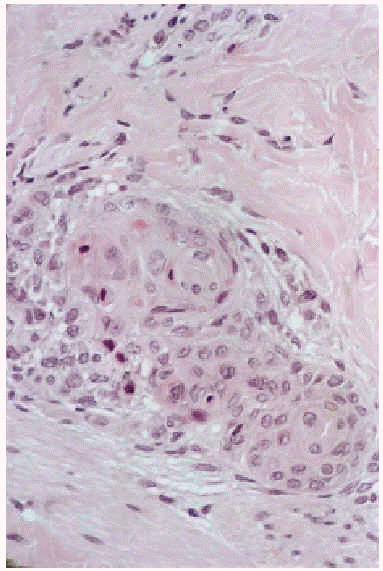

Cinco días después del final de la radioterapia la niña es hospitalizada por neutropenia febril con foco respiratorio, iniciándose tratamiento con cefepime y codeína. Al día siguiente se observó la aparición de unas placas eritematovioláceas, conformadas por micropápulas no foliculares, distribuidas en la región lumbar y en la zona del abdomen, con predilección por los bordes de la cicatriz de laparotomía (figs. 1 y 2). En el estudio histopatológico se evidenció una metaplasia escamosa madura de las porciones rectas de los conductos de las glándulas ecrinas sin afectación de los ovillos (fig. 3). Se observaban asimismo frecuentes células necróticas, queratinización de las luces y aislados queratogranulomas que entraban en contacto con la luz glandular (figs. 4 y 5). El diagnóstico histológico fue de siringometaplasia escamosa ecrina. La enferma continuó tratamiento quimioterápico, a pesar de lo cual las lesiones evolucionaron espontáneamente hacia la curación en un período aproximado de 1 mes, quedando una hiperpigmentación residual que se fue borrando paulatinamente.

Fig. 4.--Glándulas ecrinas con metaplasia escamosa e infiltrado inflamatorio periférico.

Fig. 5.--Aproximación. Transformación de las células ductales en células escamosas. Aisladas células necróticas. Queratogranuloma.